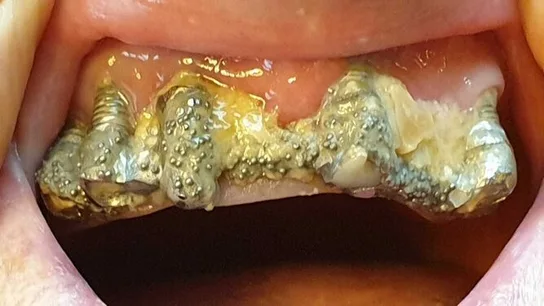

Cuenta que acudió por primera vez a la clínica en 2010 para colocarse implantes dentales en la parte superior de la boca, pero que el dentista le recomendó hacerlo también en la mandíbula inferior. Así, le extrajeron todos los dientes para susituirlos por piezas de porcelana, pero los implantes se deterioraban, se rompían y se infectaban constantemente. Por ello, le realizaron numerosas reparaciones y le recolocaron la prótesis varias veces, causándole lesiones en la boca.

Asegura que los arreglos que le hicieron en las coronas rotas a veces "duraban menos de una hora" y que, en 2016, tras más de 80 visitas al centro donde fue atendida por una decena de profesionales distintos, la clínica le comunicó que no se haría cargo de más reparaciones. A partir de entonces tendría que asumir el coste ella misma.

La mujer dice que trató de llegar a un acuerdo con el centro, pero no fue posible, por lo que denunció. Uno de los peritos que la examinó, contratado a título particular, determinó que le habían realizado "una verdadera chapuza" en la boca.